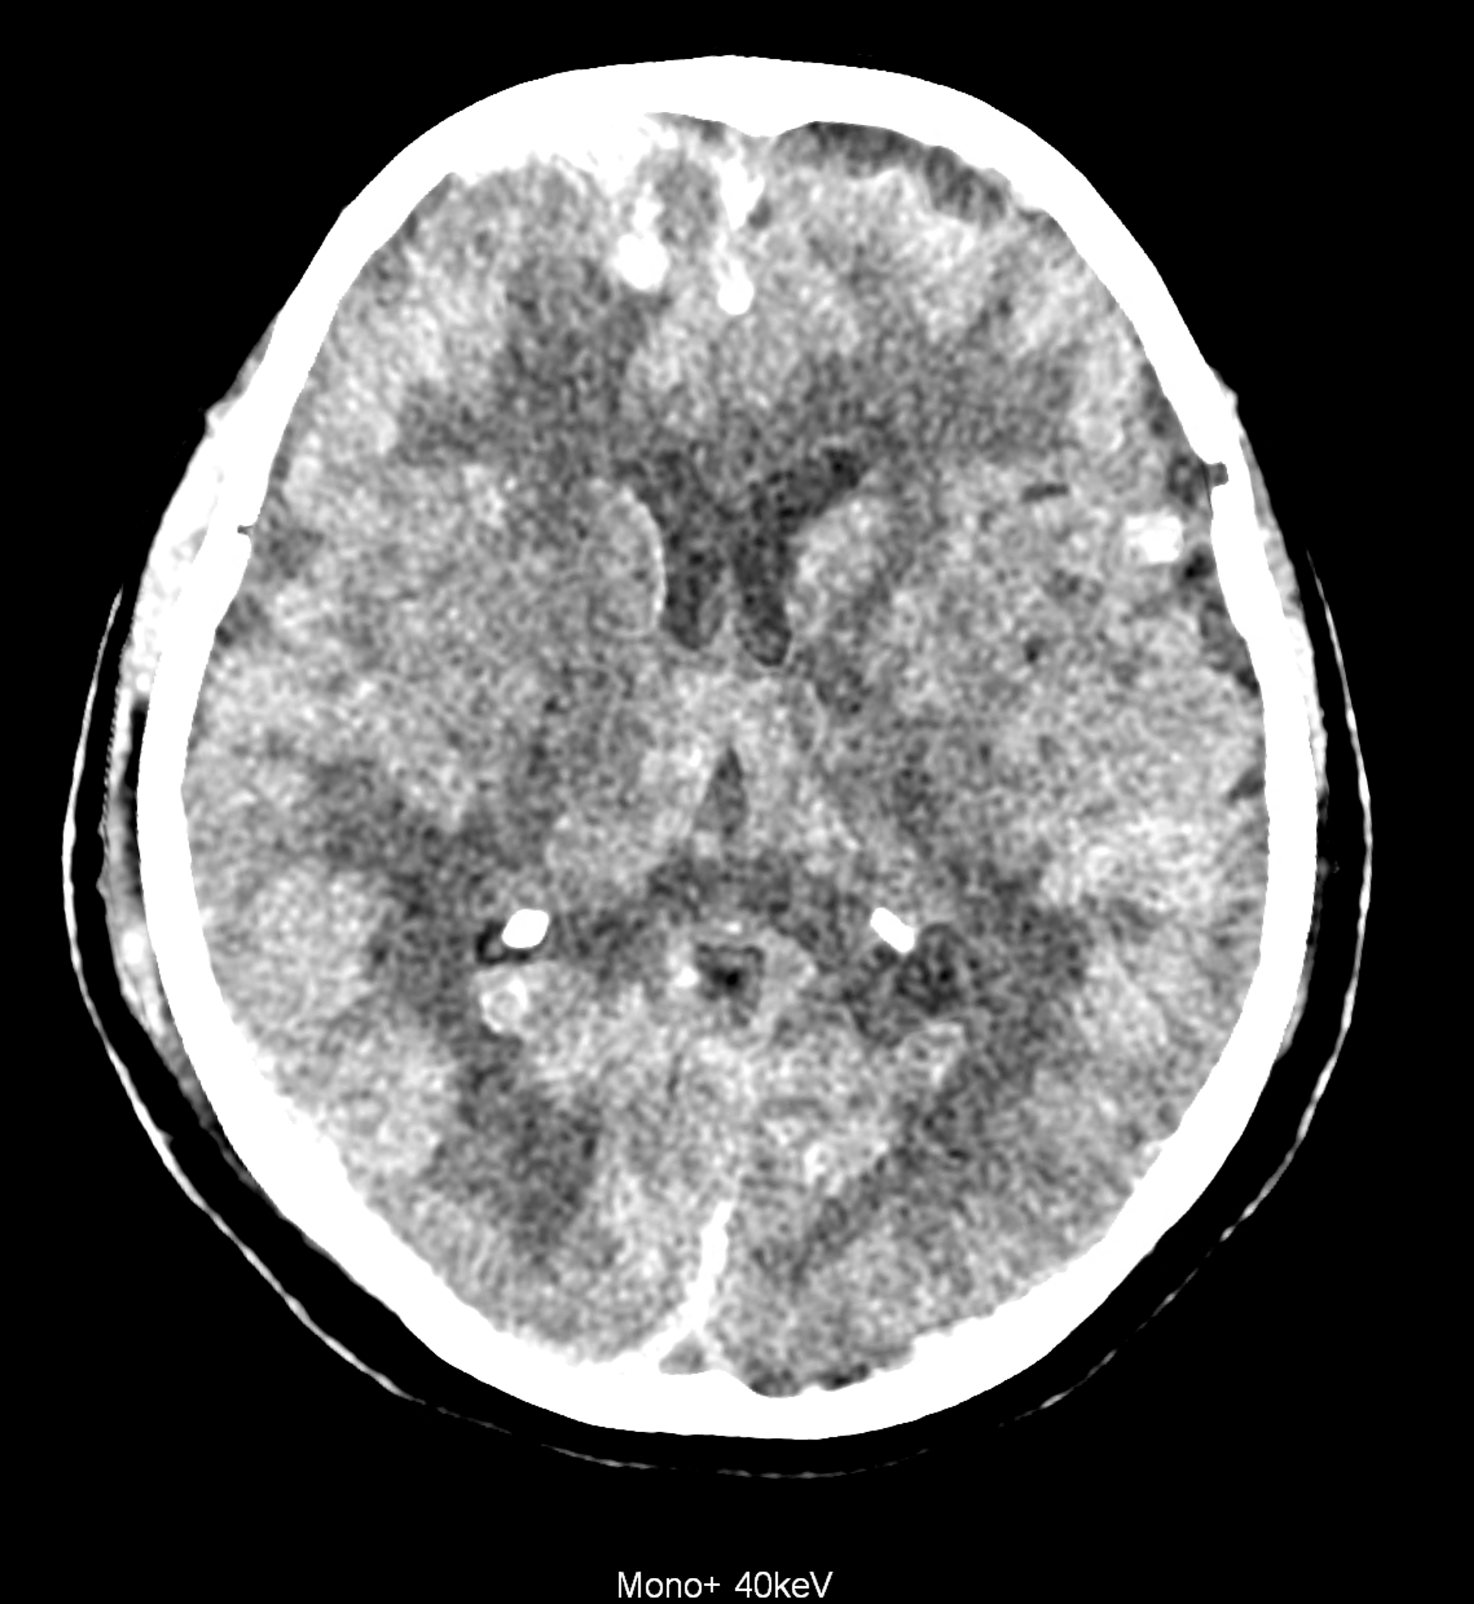

Bleeding is characterized by different absorption characteristics than healthy brain tissue (both gray and white matter) and cerebrospinal fluid. Due to the higher proportion of proteins with amino acids with disulfide bonds, the signal intensity increases at higher energies, making it possible to use monoenergetic imaging at energies above 140 keV, and/or virtual non-contrast. The hemorrhage then becomes more hyperdense, while the rest of the brain tissue acquires a uniform low signal. In addition to bleeding, areas of extracellular fluid of vasogenic origin are also imaged, i.e., in areas around contusion-type brain tissue injuries.

An example of the use of spectral imaging in complex brain injury, where contusions, diffuse axonal injury, subarachnoid hemorrhage, subdural hemorrhage, and blood in the ventricular system are present.

comparison of the images with the energies of monoenergetic reconstructions 40 keV, 67 keV (standard conventional reconstruction), 190 keV and virtual non contrast (VNC)